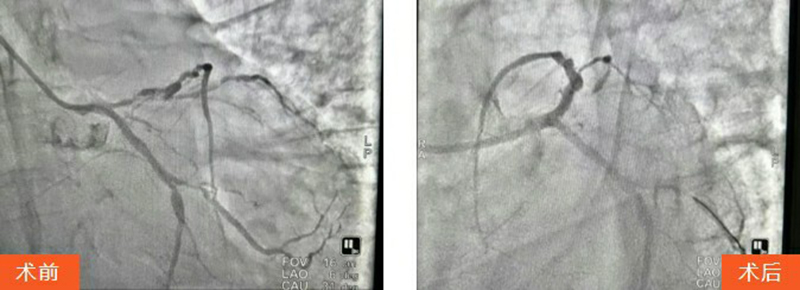

王先生被迅速送往血管介入科行急診PCI(經(jīng)皮冠狀動脈介入治療)。術(shù)中,馬建亮主任帶領(lǐng)心血管內(nèi)科專家團隊為其進行血管造影檢查,結(jié)果顯示:冠脈三支血管病變,前降支彌漫性病變伴鈣化,次全閉塞累及主干,病情極其兇險。

手術(shù)過程中患者生命體征不穩(wěn)且煩躁不安,血管介入科團隊全程安撫配合,馬建亮主任團隊果斷采用球囊擴張病變血管,成功植入2枚冠脈支架,最終使患者轉(zhuǎn)危為安。